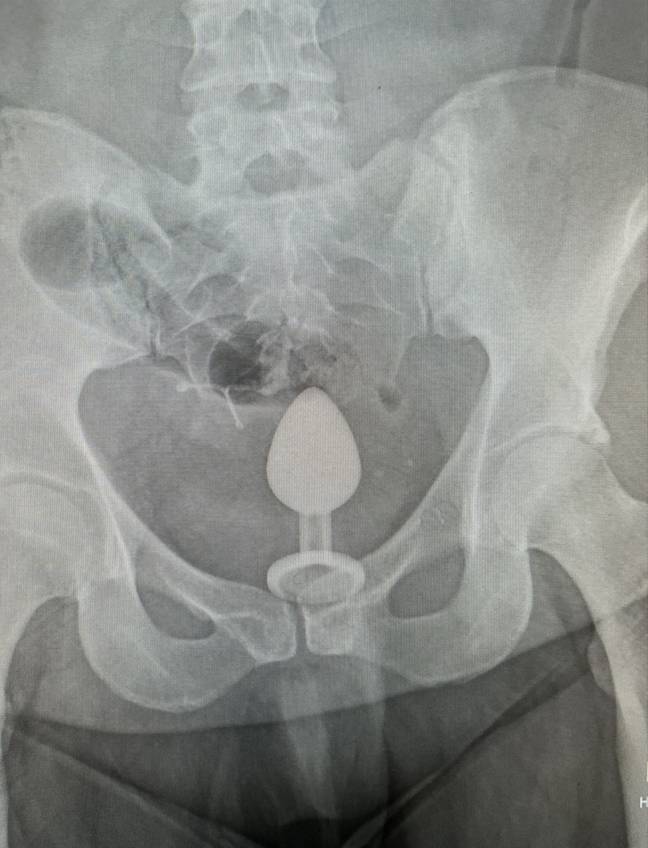

After getting nowhere, Gigi called 111 and was advised by an NHS call handler to go to A&E, where an X-ray revealed the toy was ‘so far up’ that even the doctors ‘didn’t know how to get it out’. They suggested surgery as the safest option, but one doctor decided to have a fish around with his hand first.